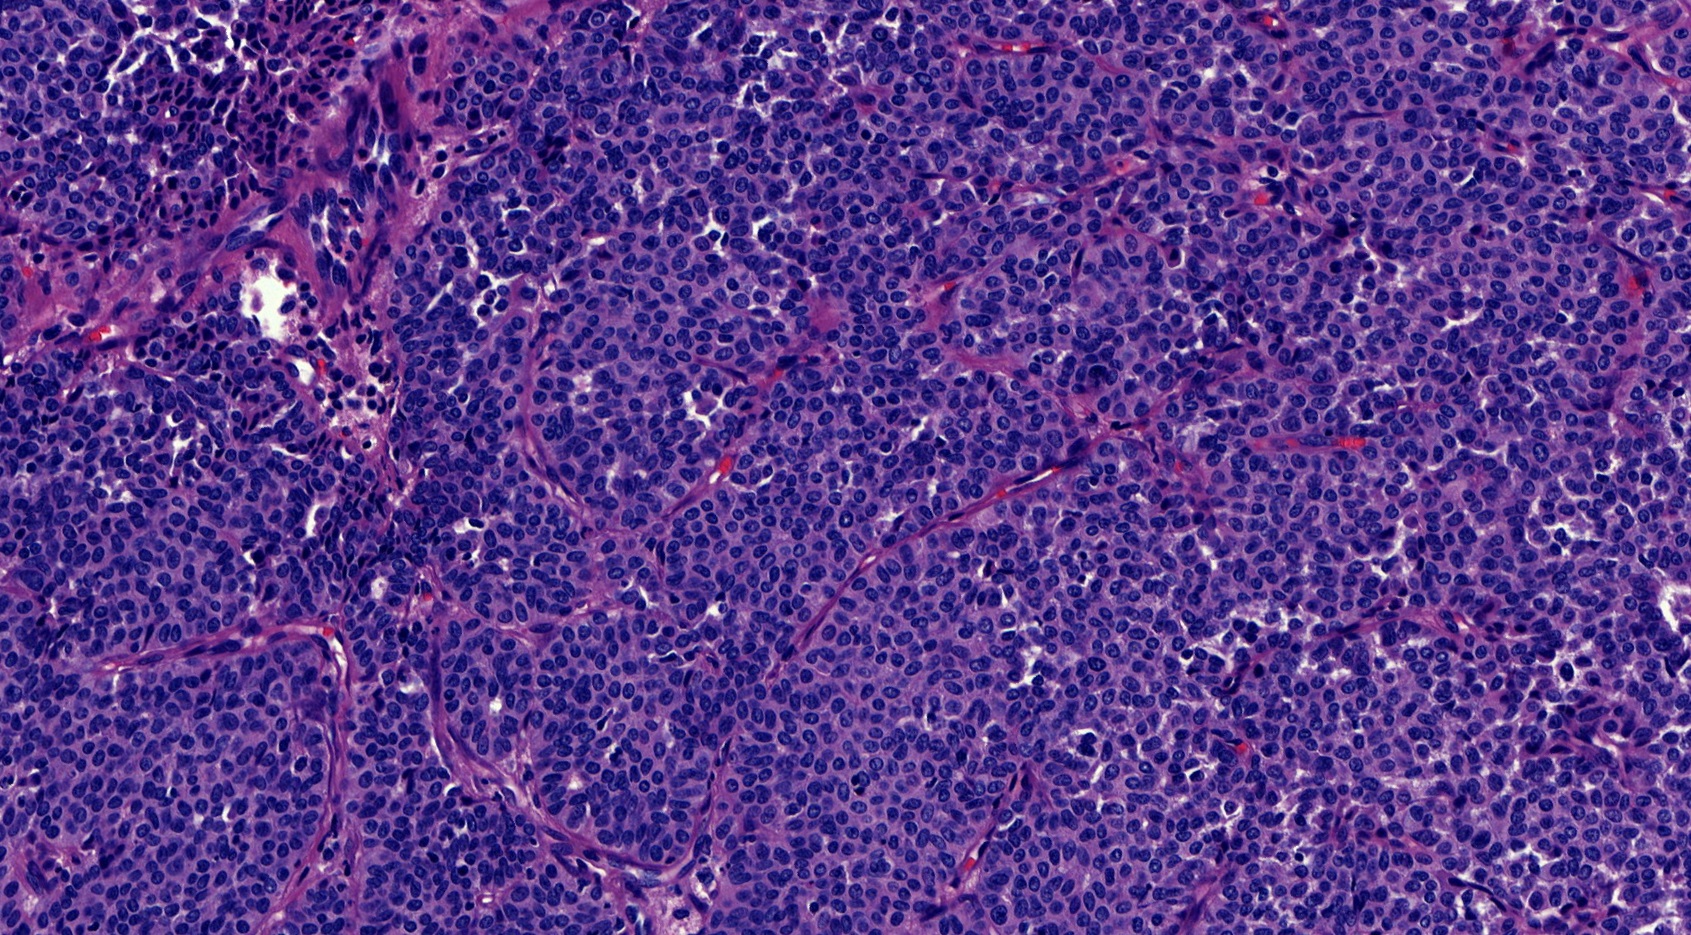

- Papillary tumor with pushing borders, may be within a cystically dilated duct, surrounded by a thick fibrous capsule (Histopathology 2008;52:20, Mod Pathol 2021;34:1044, Virchows Arch 2022;480:5)

- Delicate papillary fronds with fibrovascular cores lined by cuboidal to columnar epithelial cells with low to intermediate grade atypia

- Cribriform and solid architecture may be present

- Low mitotic activity (average 3 mitoses per 10 high power fields [HPFs]) (Am J Surg Pathol 2011;35:1)

- Most show complete lack of myoepithelial cells along the papillae and around the periphery of the tumor (Am J Surg Pathol 2006;30:1002, Am J Surg Pathol 2011;35:1)

- High grade invasive carcinoma with EPC features (Histopathology 2015;66:740, Histol Histopathol 2019;34:137)

- High grade cytologic atypia with nuclear pleomorphism, frequent mitotic figures (mean mitotic activity 22 per 10 HPFs) and occasional necrosis

Microscopic (histologic) images

Contributed by Kristen E. Muller, D.O. , Mariel Molina Nunez, M.D. and Julie Jorns, M.D. (Case #518)